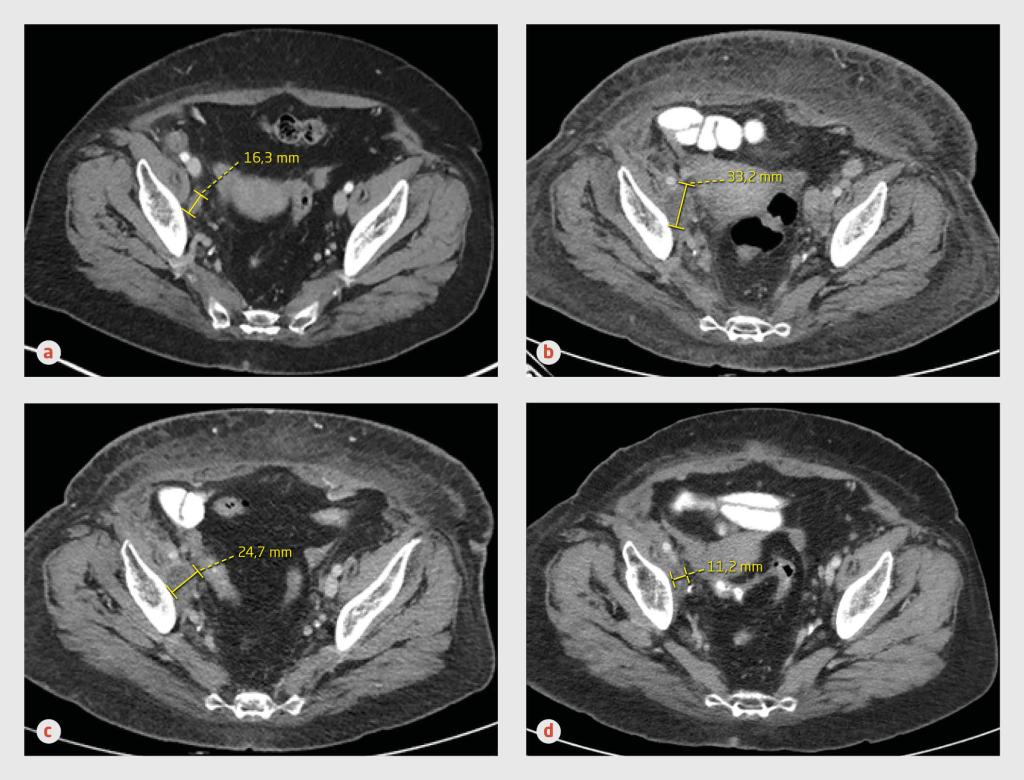

Transversale CT-opnames van het abdomen van een 63-jarige vrouw met een lymfogeen en cutaan gemetastaseerd melanoom. (a) Op het moment dat gestart wordt met immuuntherapie met nivolumab is mediaal van het os ilium een pathologische lymfeklier met een diameter van 16 mm zichtbaar. (b) 6 maanden na aanvang van de immuuntherapie blijkt de lymfekliermetastase in grootte te zijn toegenomen. (c) 6 weken later is de lymfekliermetastase in grootte afgenomen. (d) 10 maanden na aanvang van de immuuntherapie is een complete remissie bereikt.

Bij responsevaluatie gedurende de opname namen de axillaire en intra-abdominale lymfekliermetastasen zowel in aantal als in grootte toe. De cutane metastase was echter wel afgenomen in grootte. Om die reden, maar ook omdat we geen aanwijzingen hadden voor een immuun-gemedieerde oorzaak van de decompensatio cordis, besloten wij de immuuntherapie te continueren.

6 weken later waren de lymfekliermetastasen fors in grootte afgenomen en na een behandelduur van 10 maanden was een complete remissie bereikt. Wij stopten de behandeling met nivolumab. Bij poliklinische controle 13 maanden nadat de immuuntherapie was gestopt, voelde patiënte zich uitstekend en waren…